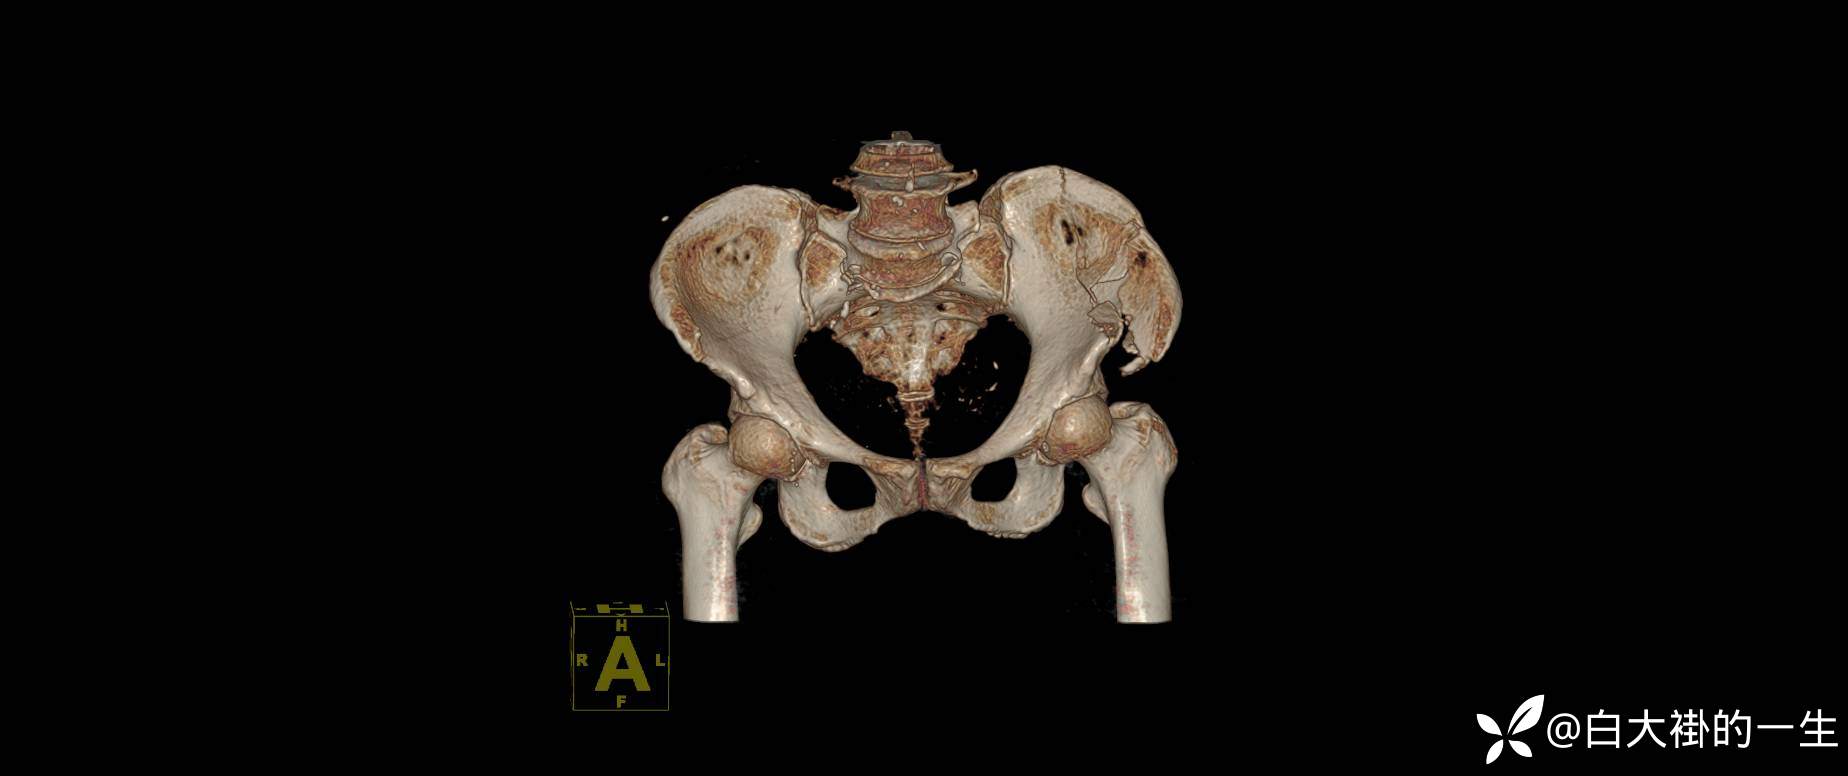

2024-08-03外院DR:左髂骨粉碎性骨折。

入院诊断:1.左髂骨粉碎性骨折;2.左髋部皮肤擦伤。

影像学如图: